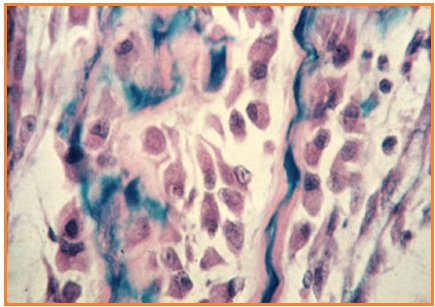

Epitel pipih berlapis banyak

• Tersusun atas berlapis-lapis sel yang berbentuk pipih.

• Berfungsi sebagai proteksi.

• Contoh: Telapak kaki, hidung, mulut, esofagus dan vagina.